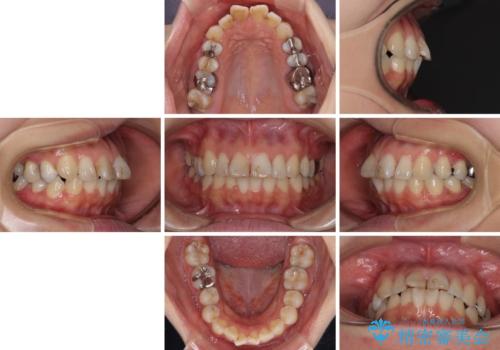

- 前歯のデコボコを治したいとのことで来院された患者様です。

上下顎ともに歯列全体の後方移動とIPR(歯と歯の間を削る)によってデコボコが解消するように設計し、インビザラインにより治療を行うこととしました。

しっかりと装着時間を守ってくださったのですが、途中妊娠にともなう悪阻や出産といったイベントがあり、予定よりも治療期間が長くなりました。